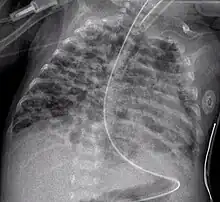

A chest film after insertion of an implantable cardioverter-defibrillator, showing the shock generator in the upper left chest and the electrical lead inside the right heart. Note both radio-opaque coils along the device lead.